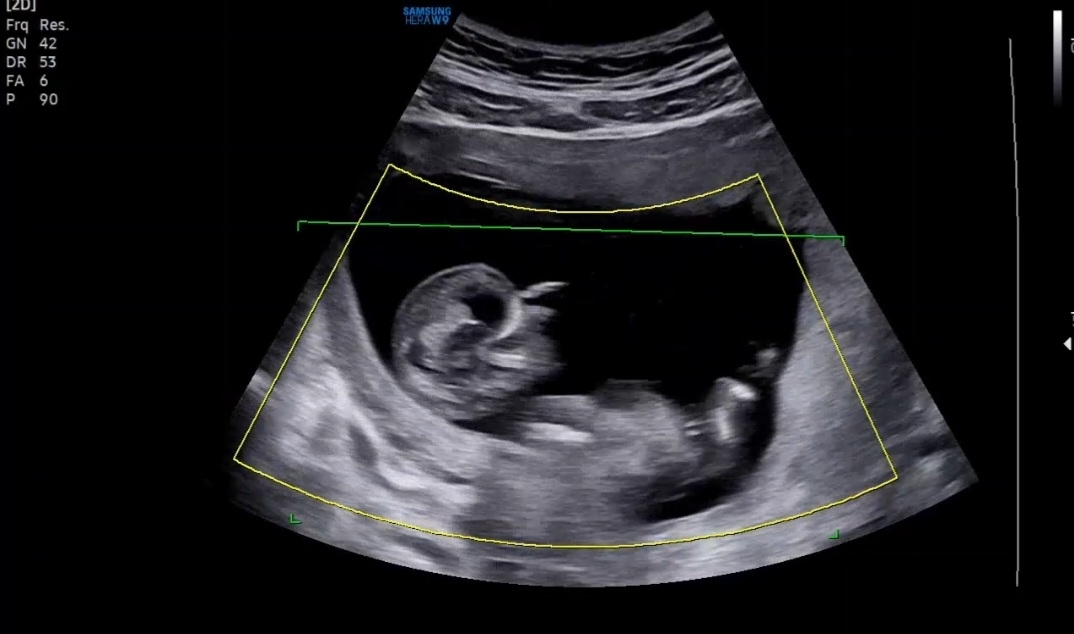

각도법 봐주세요

성별너무너무 궁금해요!!ㅎㅎ 각도법 고수님들 봐주세요